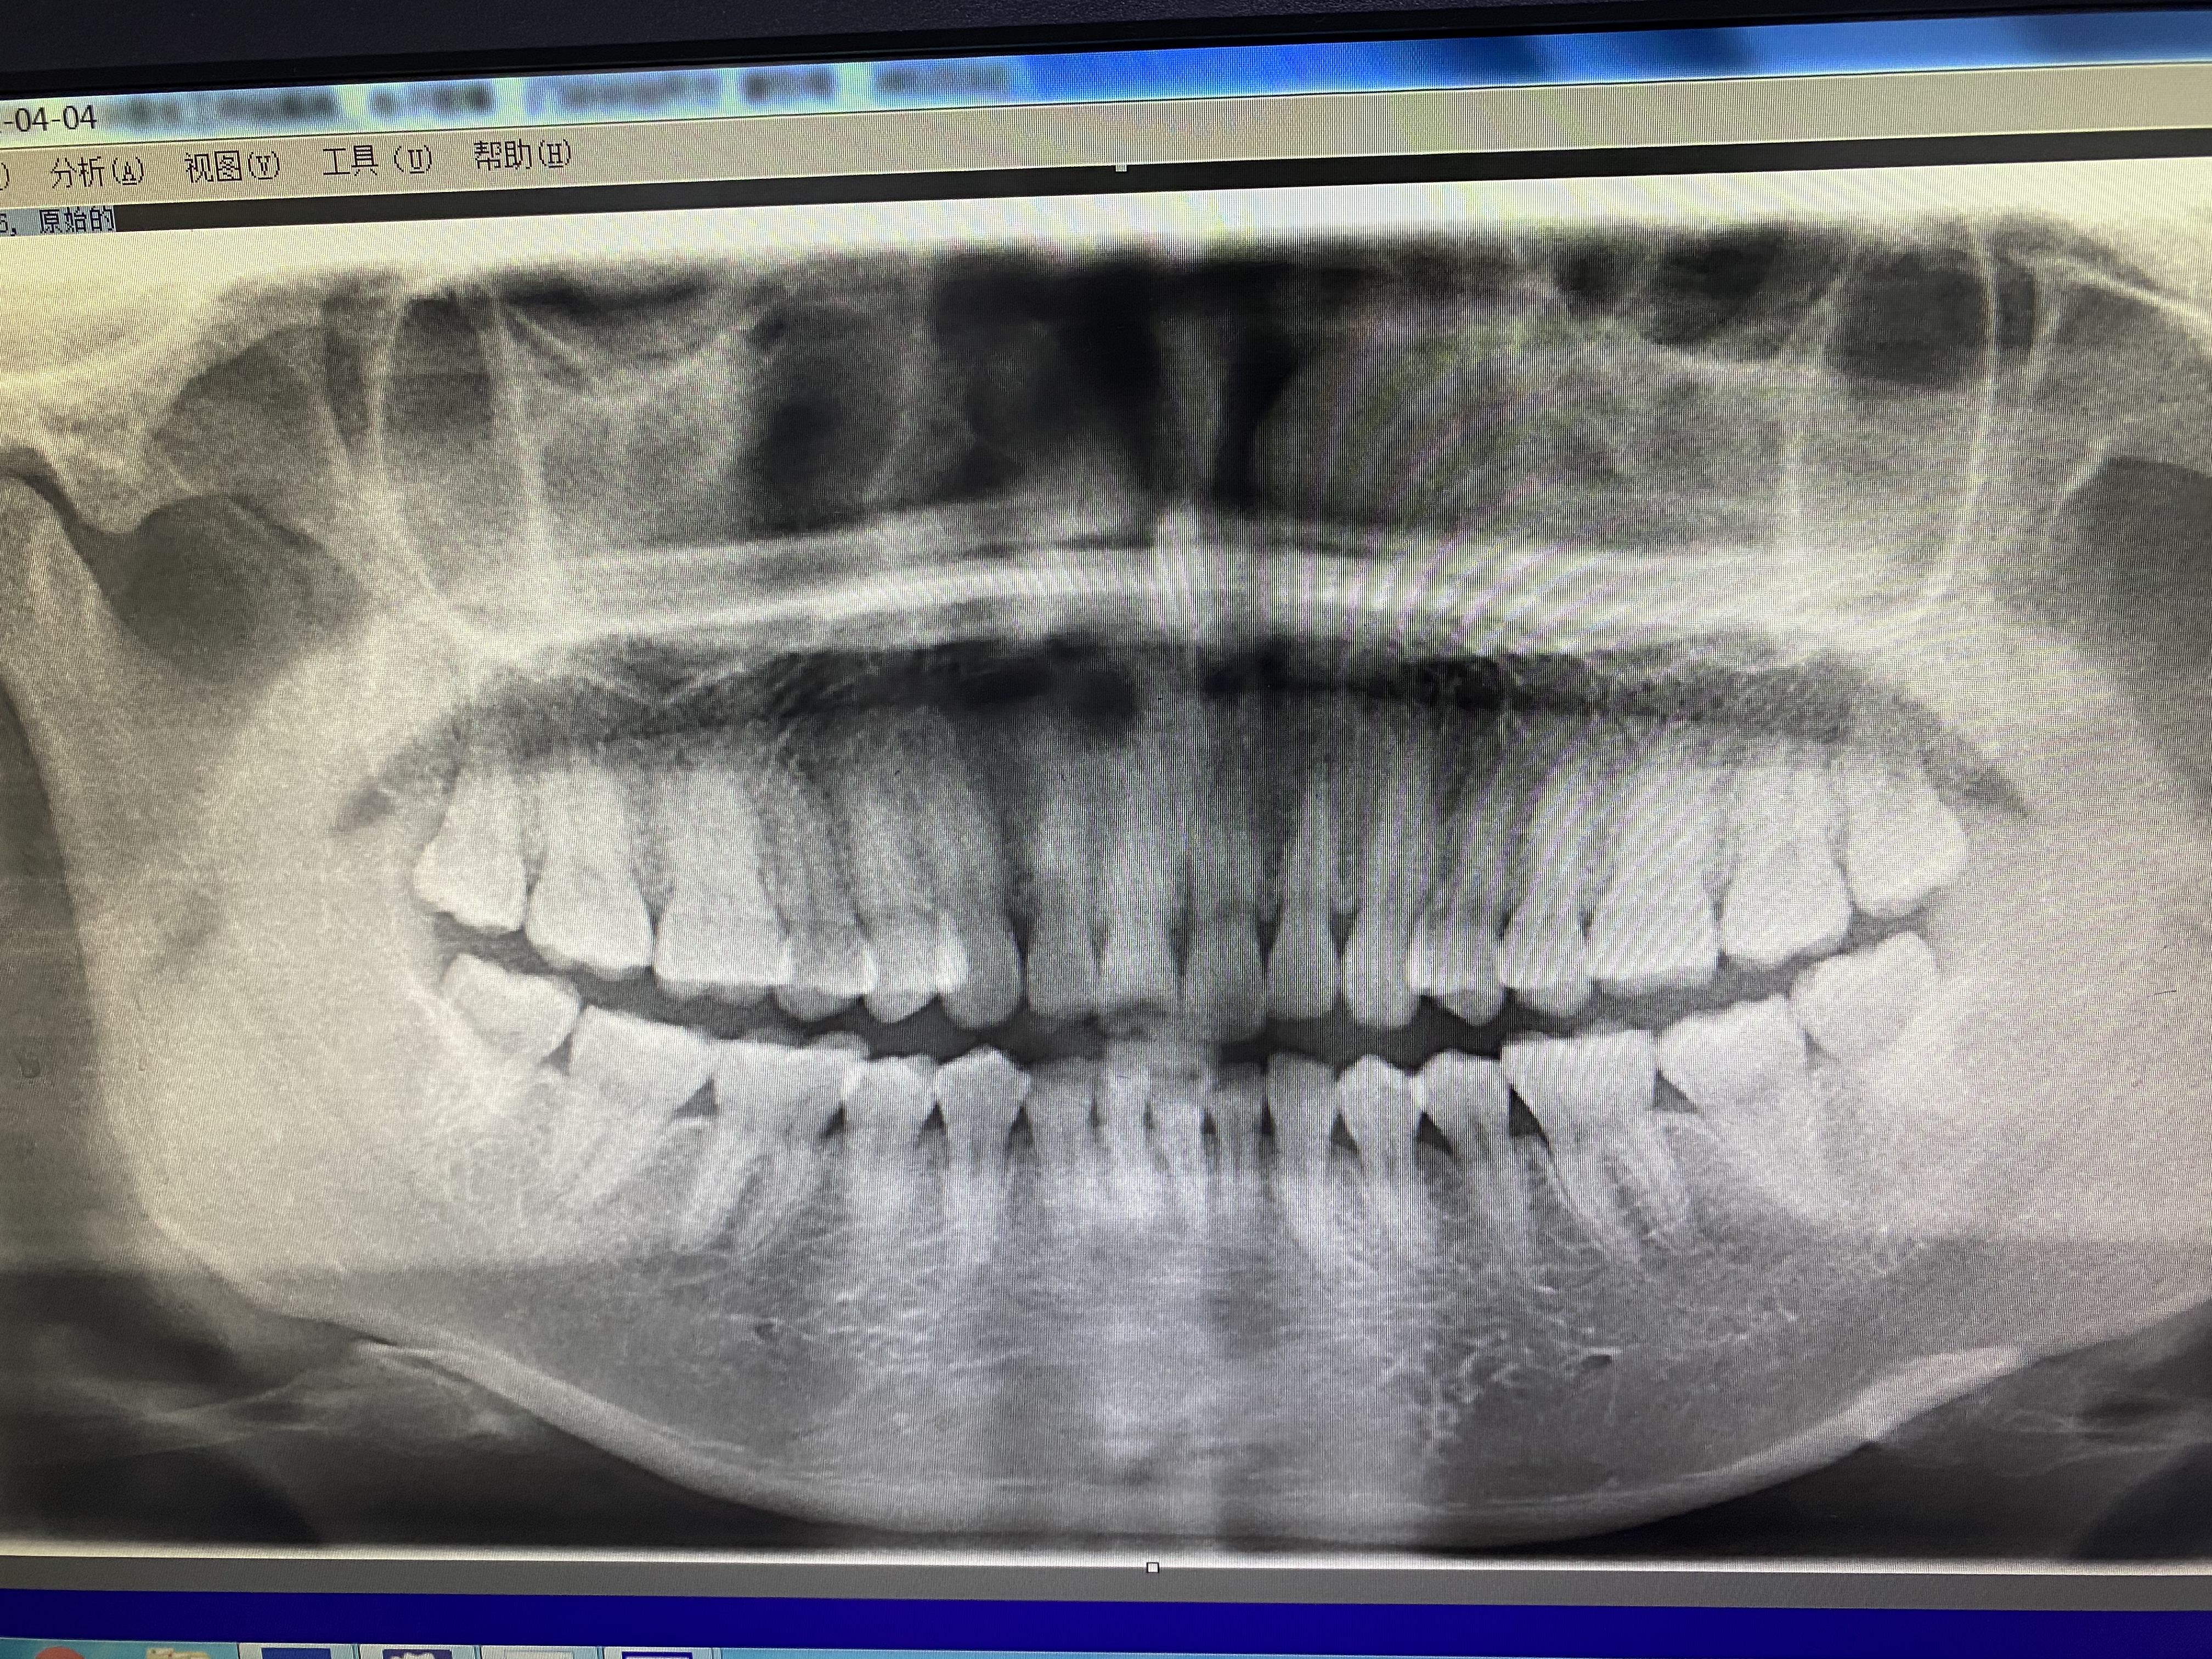

回家的路上,我看到了口腔科的普通医师。到了预约的时间,去拍了照片。下面是我拍的牙齿照片。

我的牙齿

拍完照片以后就定下来了,下次拔牙的时间。我的牙齿长得还算周正,智齿长得也特别好,但是龋齿了,面临的是要么补牙,要么拔牙,因为智齿在最里面,刷牙很难照顾到他,而且也没有什么用,干脆就拔了吧。其实当天也可以拔,但是没有想好。而且当时比较忙,应该没有时间好好休息恢复。这里要注意的是,拔牙的时候,要错开大姨妈的时间,因为抵抗力比较差。所以要合理的避开。还要避开比较繁忙的工作,要不然肯定是要上火的。